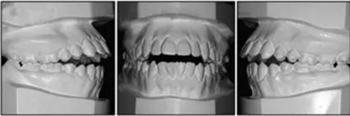

口內(nèi)相示:口腔衛(wèi)生可,下頜前牙區(qū)輕度擁擠伴齦上牙石,無(wú)齲齒、牙齦炎;開(kāi)合,覆蓋5mm,休息時(shí)舌后退位,吞咽時(shí)舌前伸。

口內(nèi)相及模型:雙側(cè)磨牙、尖牙I類(lèi)關(guān)系,良好的牙尖交錯(cuò)關(guān)系,覆合、覆蓋正常。